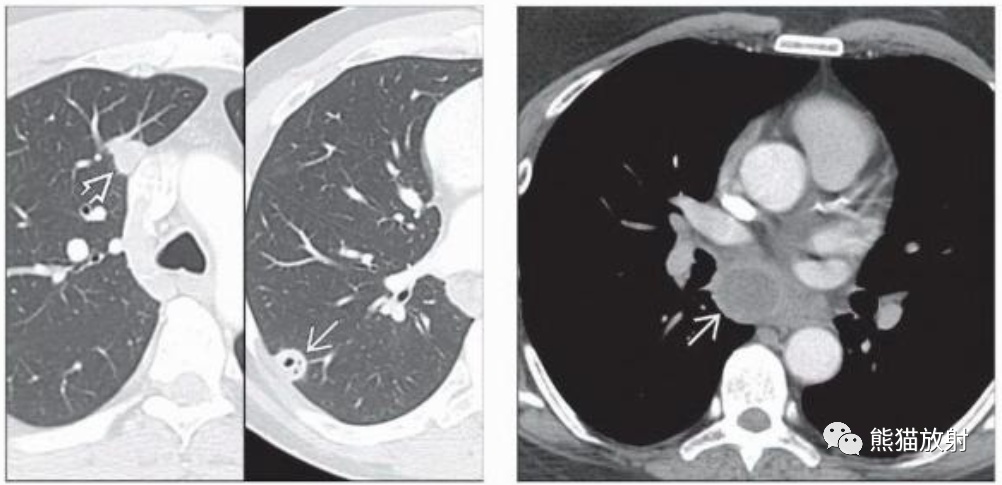

(左) 艾滋病并发肺隐球菌病。CT显示右肺实性和空洞性肺结节。肺隐球菌病最常见的表现是多发性肺结节。空洞在较大的结节和免疫功能低下的患者中更为常见。

(右) 同一患者,气管隆突下淋巴结肿大,表现为环形强化和中心低密度。

(左)免疫功能低下的肺隐球菌病患者,PA胸片显示右下肺野见一空洞性肿块,内见气液平面。

(右)同一患者,CECT肺窗和软组织窗图像显示右肺下叶空洞性肿块,内见气液平面,提示脓肿形成。邻近肺实质可见片状磨玻璃影(弯箭)。